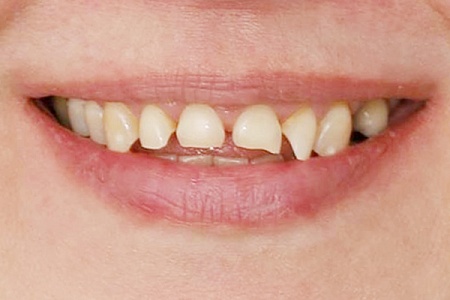

Работы наших врачей